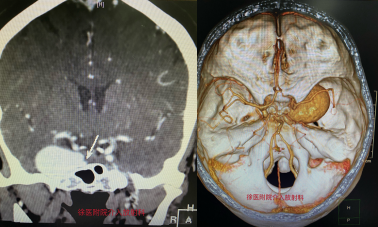

患者王阿姨因右眼腫脹3月余至當(dāng)?shù)蒯t(yī)院就診,檢查發(fā)現(xiàn)顱內(nèi)血管占位,考慮巨大動(dòng)脈瘤可能性大。轉(zhuǎn)至徐醫(yī)附院后,介入科徐浩主任、崔艷峰主任立刻組織醫(yī)療團(tuán)隊(duì)對(duì)患者進(jìn)行頭頸部CTA及腦血管造影檢查,檢查結(jié)果令人吃驚。這是一例較罕見(jiàn)的巨大頸內(nèi)動(dòng)脈海綿竇段動(dòng)脈瘤,瘤體大小約34mm*24mm,治療過(guò)程中一旦破裂出血,死亡率極高。

對(duì)于巨大顱內(nèi)動(dòng)脈瘤,傳統(tǒng)支架輔助下彈簧圈填塞或者封閉載瘤動(dòng)脈都會(huì)對(duì)患者產(chǎn)生不良影響,復(fù)發(fā)率高,易產(chǎn)生腦缺血并發(fā)癥。徐浩主任、崔艷峰主任攜團(tuán)隊(duì)成員仔細(xì)研判病情并深入討論后決定使用較為前沿的血流導(dǎo)向支架技術(shù)。血流導(dǎo)向支架(Pipepline支架)是一種低網(wǎng)孔率和高金屬覆蓋率支架,可改變血流方向并促進(jìn)支架內(nèi)的內(nèi)皮細(xì)胞增生,通過(guò)促使瘤頸內(nèi)膜化達(dá)到修復(fù)載瘤動(dòng)脈的作用。該項(xiàng)技術(shù)是目前國(guó)際上較為先進(jìn)的治療復(fù)雜顱內(nèi)動(dòng)脈瘤的主要治療手段。